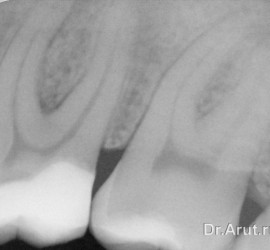

Лечение пульпита. При лечении пульпита перед врачом встают следующие задачи: избавление больного от болевых ощущений, ликвидация инфекционно-токсического очага в пульпе зуба, восстановление формы и функции зуба. Первую помощь больному острым пульпитом может оказать средний медработник или врач любого другого профиля. Она заключается в назначении внутрь обезболивающих препаратов типа анальгина, амидопирина, […]